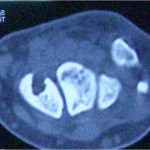

Introduction: The ischiogluteal bursa is an inconstant anatomical finding located between the ischial tuberosity and the gluteus maximus. Ischiogluteal bursitis is a rare disorder.

Case Report: We report the case of a 43-year-old female patient with bilateral calcifying ischiogluteal bursitis. The patient had no relevant medical history of systemic illness or major trauma to the buttock. After aspiration of both ischiogluteal bursitis which delivered calcareous deposits and instillation of a mixture of 1cc betamethasone (6 mg) and 4 cc of 1% lidocaine the patient was out of any complaints.

Conclusion: Calcifying ischiogluteal bursitis is a rare entity but easily diagnosed on radiographs. Aspiration and local steroid instillation give good relief from symptoms.